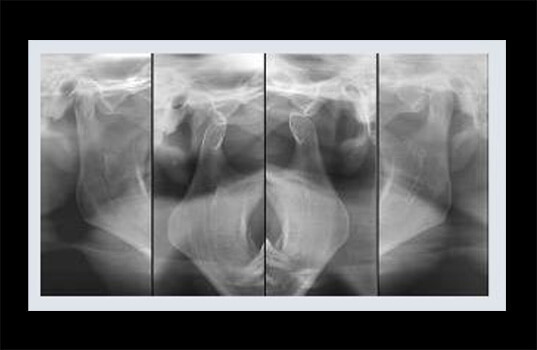

O exame ATM (Articulações Temporo-Mandibulares) é usado na odontologia para avaliar a saúde das articulações que conectam a mandíbula ao crânio. Estas articulações são importantes para a mastigação, fala e movimento da mandíbula. Problemas nessas articulações podem causar dor de ouvido, dor de cabeça, dor facial e dificuldade para abrir a boca.